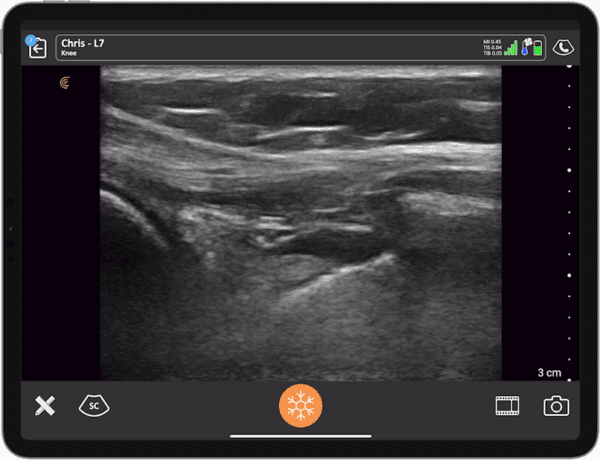

Reimagining MSK Education: Teaching Ultrasound for the Next Generation of Clinicians

Join leading physical therapy educators Dr. Mike Voight and Dr. Chris Wolfe from Belmont University, for a live webinar exploring how handheld ultrasound is transforming MSK education—and why more institutions are integrating it into their programs.

Whether you’re training future clinicians or practicing in the field, this webinar will show how handheld ultrasound can elevate MSK care and close the diagnostic gap in physical therapy, and beyond.